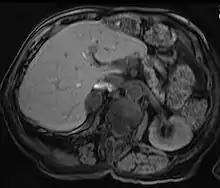

Adrenal adenoma in a patient with Conn syndrome | |

Due to their asymptomatic nature, most reported cases of adrenal adenomas have been discerned fortuitously through autopsy, or during medical imaging, particularly CT scan (computed tomography) and magnetic resonance imaging. Hence, they have earned the title incidentaloma referring to small adenoma discovered incidentally.[9] Though adrenocortical adenomas are considered challenging to differentiate from the normal adrenal cortex, they appear as well-circumscribed lesions once isolated.

Imaging Diagnostics